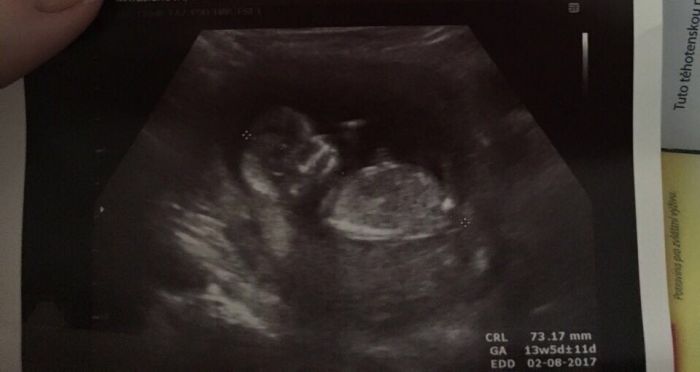

dneska večer v šest mam screening. .tak se tesim a bojim zároveň. .

Ahoj zensky . Tak jsme doma z prohlidky. Miminko je v poradku. Mame 7,5 cm a krasne na me maval. :-) ve stredu prenatal. Tak me padl kamen ze srdce.